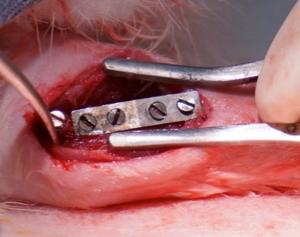

Biodegradable Biomaterials Related Research

In the area of biomaterials, Dr. Datta’s group’s goal is to create implantable devices and regenerative therapies by merging advances in biology, engineering, and materials sciences. Particularly, he aims to develop materials that will not only be compatible with patients, but can also direct the cellular responses of the patient in a desired manner. In this direction, his research is directed in identifying a novel class of suitable load bearing, non-toxic biocompatible and biodegradable metal alloys aided by density functional theory (DFT) calculations as a hard tissue substitute for orthopedic and craniofacial applications. Processing of near-net shape biocompatible and biodegradable porous 3D scaffolds exhibiting controlled corrosion and mechanical properties mimicking normal bone without eliciting any toxicity while regenerating new bone is under research and development by powder metallurgy (PM) and additive manufacturing (AM) processing techniques. In addition, Dr. Datta’s research has directed towards development and optimization of stable organic and inorganic bioactive coatings on implants to decrease the alloys’ corrosion rate and hydrogen evolution as well as increase the alloys’ surface bioactivity, thus increasing the clinical relevance of biodegradable alloys. Surface functionalized micro- and meso-porous bio-composites is also under study for tunable delivery of biologics and drugs from the regenerative bone scaffolds.